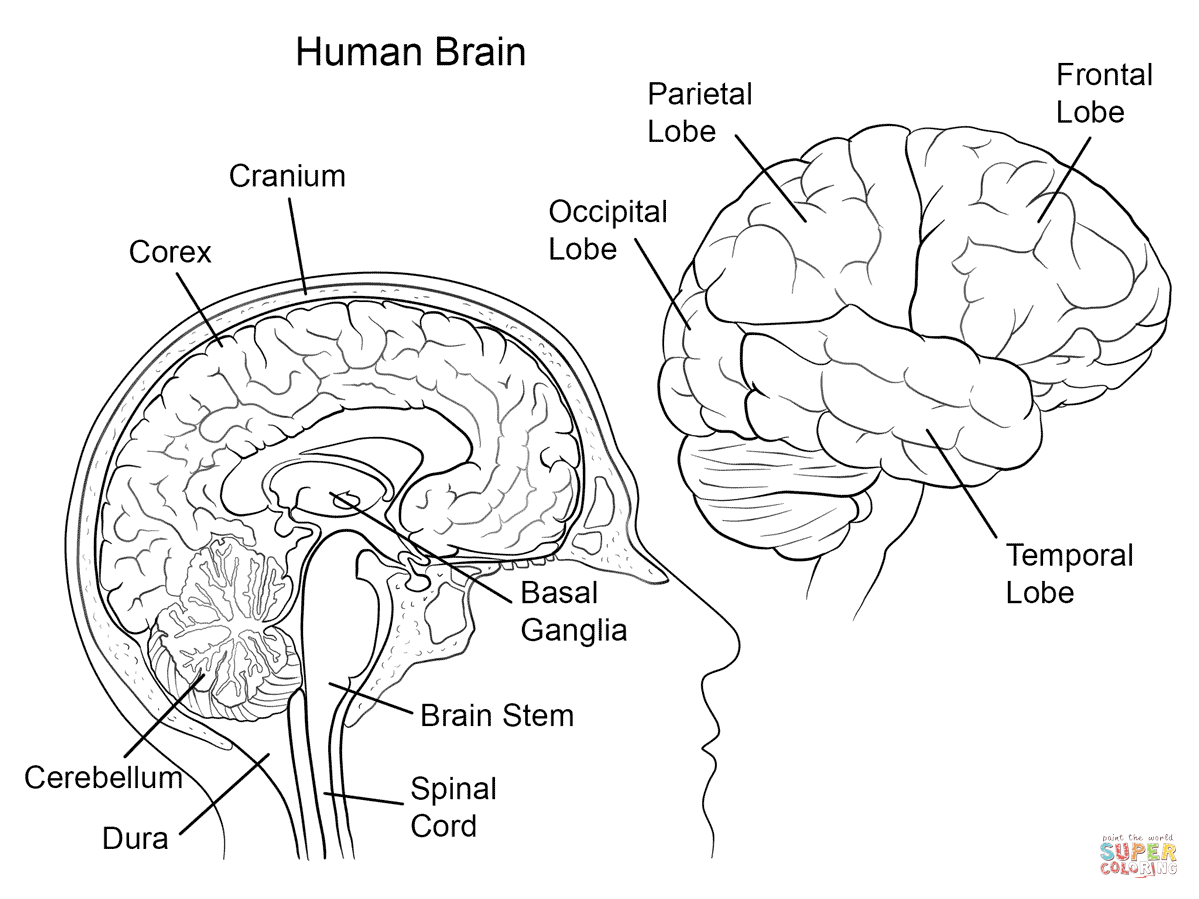

Source: supercoloring.com

Source: supercoloring.com